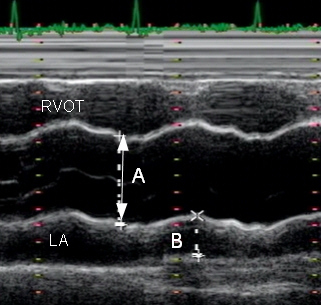

Aortic Root diameter?

A

2.0 - 3.7 cm

LA

A

1.9 - 4.0 cm